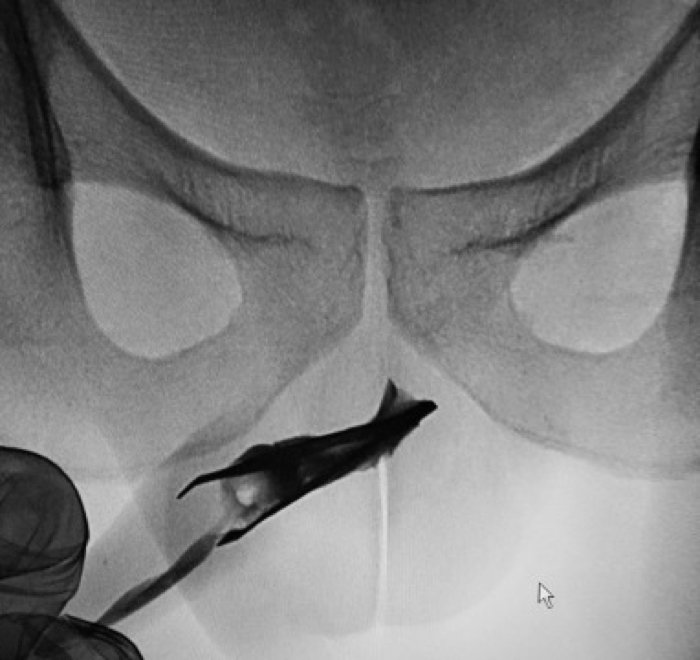

Саудовец прожил четыре года с щипцами в пенисе

Мужчина из Саудовской Аравии ввел себе в уретру щипчики для волос и проходил так четыре года, пока не обратился к врачам. Его неудачный эксперимент над собственным телом урологи описали в статье в журнале Urology Case Reports.

22-летний молодой человек обратился к врачам, чтобы избавиться от щипчиков для волос, которые он ввел в уретру еще в 18-летнем возрасте. При этом его не беспокоила ни боль, ни какие-либо специфические симптомы. Рентгенограмма показала, что щипцы длиной около 8 см находятся в передней части мочеиспускательного канала.

Врачам удалось избежать хирургической операции. Вместо этого они прибегли к эндоскопической процедуре, буквально «выдавив» щипцы наружу. Опасность представляли острые кончики щипцов, которые могли травмировать слизистую, так что врачам пришлось сначала соединить кончики, а затем уже вытаскивать щипцы.

Никаких осложнений после этих манипуляций у пациента не возникло. Врачи порекомендовали мужчине обратиться к психиатру, но тот отказался.